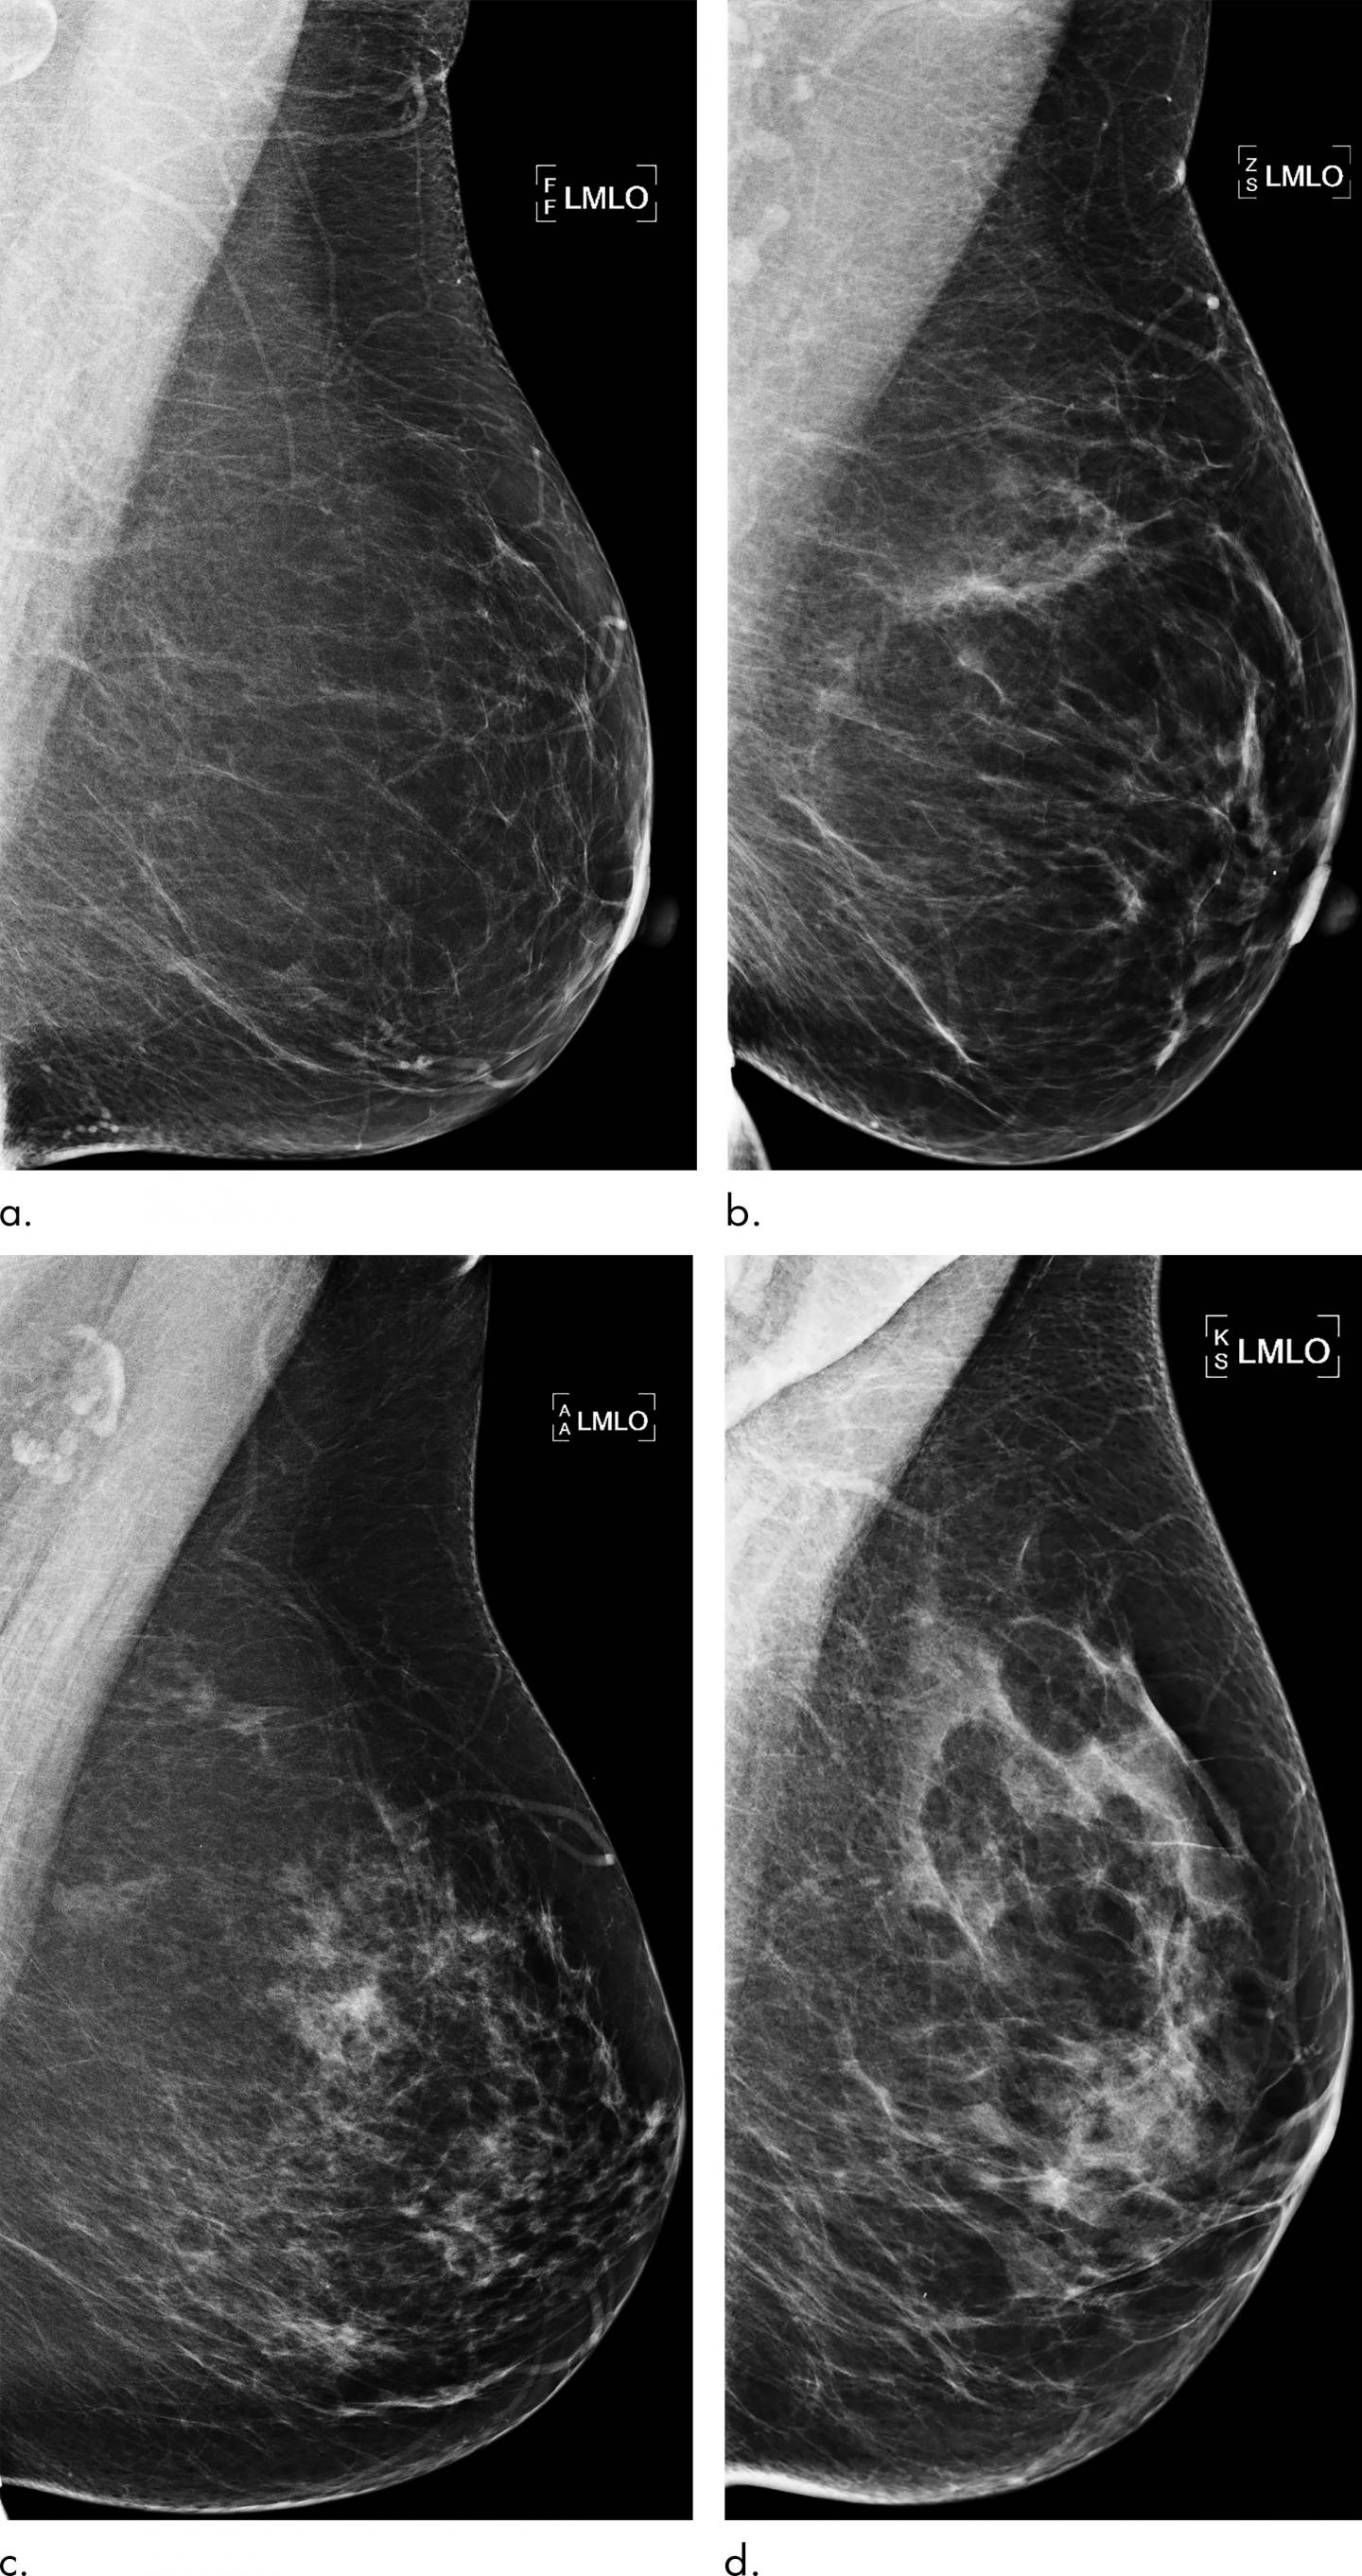

High breast density, or a greater amount of glandular and connective tissue compared to fat, is considered a risk factor for cancer. While density may be incorporated into risk assessment, current prediction models may fail to fully take advantage of all the rich information found in mammograms. This information has the potential to identify women who would benefit from additional screening with MRI.

Dr. Dembrower and colleagues developed a risk model that relies on a deep neural network, a type of AI that can extract vast amounts of information from mammographic images. It has inherent advantages over other methods like visual assessment of mammographic density by the radiologist that may not be able to capture all risk-relevant information in the image.

The new model was developed and trained on mammograms from cases diagnosed between 2008 and 2012 and then studied on more than 2,000 women ages 40 to 74 who had undergone mammography in the Karolinska University Hospital system. Of the 2,283 women in the study, 278 were later diagnosed with breast cancer.

The deep neural network showed a higher risk association for breast cancer compared to the best mammographic density model. The false negative rate--the rate at which women who were not categorized as high-risk were later diagnosed with breast cancer--was lower for the deep neural network than for the best mammographic density model.

"The deep neural network overall was better than density-based models," Dr. Dembrower said. "And it did not have the same bias as the density-based model. Its predictive accuracy was not negatively affected by more aggressive cancer subtypes."